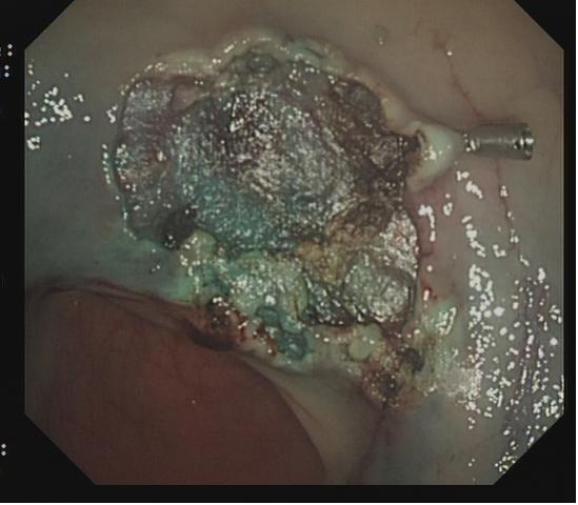

对于直径大于2 cm且需一次性切除病变、抬举征阴性的腺瘤及部分早癌、EMR 残留或复发治疗困难者,可以实行 ESD 治疗,一般步骤为:

1.内镜染色后明确病灶边界,环周标记(病灶边界较为清晰者也可不标记),

2.黏膜下注射,使病灶抬举明显。

3.部分或环周切开黏膜,显露黏膜下层。

4.沿着黏膜下层疏松结缔组织,逐渐剥离病变组织。

5.仔细观察创面,对血管处进行处理,预防并发症。

6.对切除后的标本进行处理后,送病理检查。

上下滑动查看△图5 大型病变的ESD治疗。